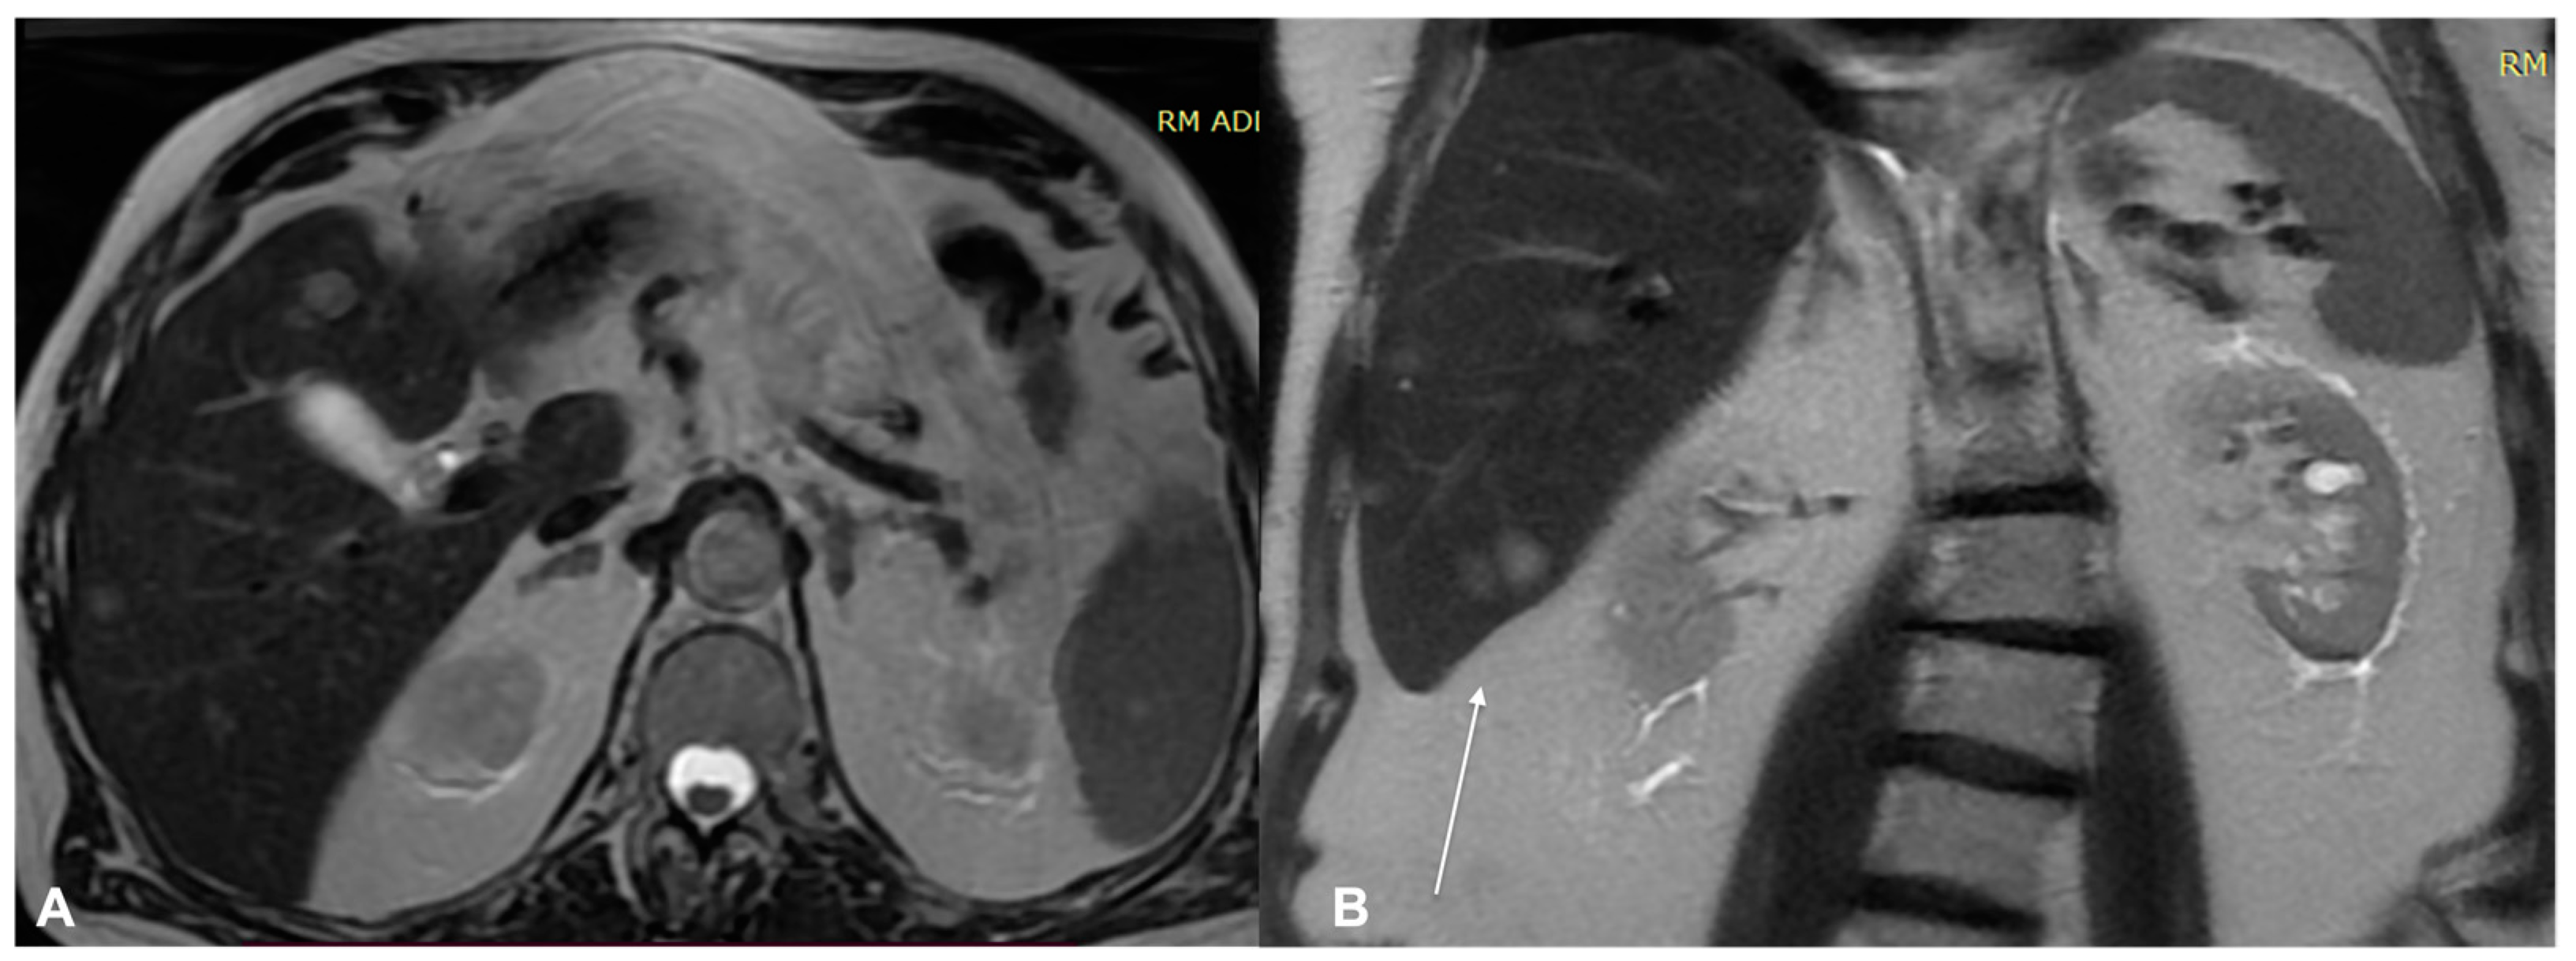

2. Diagnostic Imaging and Non-Melanoma Skin Cancer

3. Diagnostic Tools and Non-Melanoma: Staging and Surveillance